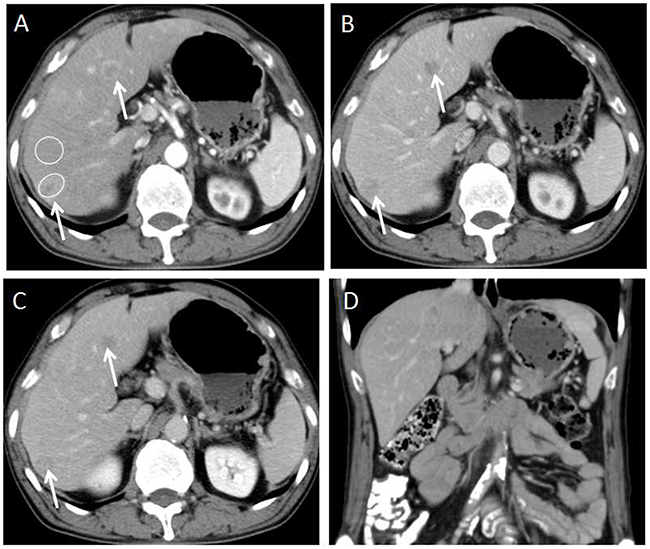

Figure 2: 58-year-old male with G2 colon NET. (A) Axial CT image on hepatic arterial phase demonstrates multiple hyper enhanced liver metastases in the liver(arrows). Two oval shaped ROIs were placed on the largest lesion and adjacent normal liver. The metastasis-to-liver ratios on hepatic artery phase and portal venous phase were 115.7% and 84.8% respectively. (B, C) Axial CT images on portal venous phase and equilibrium phase show the liver metastases being hypo enhanced that meets the washout enhancement pattern(arrows). (D) Coronal CT image on the portal venous phase shows absent of lymphadenopathy.